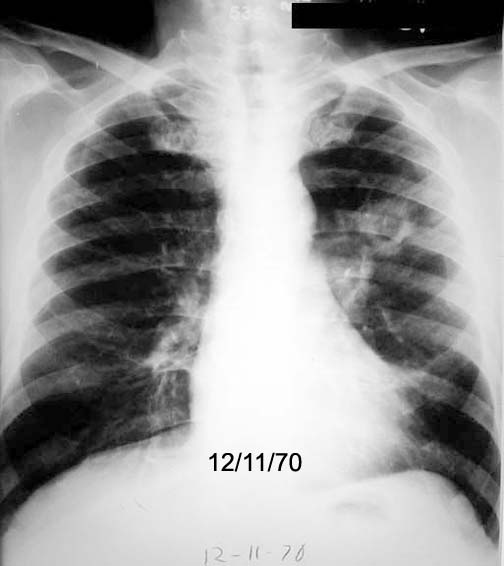

Case 8

Lateral

Follow up